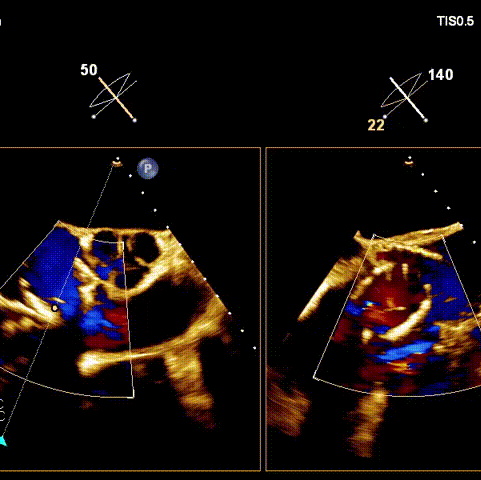

術(shù)后超聲

術(shù)前經(jīng)過(guò)全面系統(tǒng)的評(píng)估后,考慮患者存在高齡、心功能減低、三尖瓣瓣環(huán)重度擴(kuò)張(三尖瓣極重度反流)等高危因素,因此廈心結(jié)構(gòu)心團(tuán)隊(duì)聯(lián)合超聲心動(dòng)、麻醉及護(hù)理團(tuán)隊(duì),制定了詳盡的圍術(shù)期治療方案及術(shù)中治療難點(diǎn)預(yù)案。術(shù)中,由王焱院長(zhǎng)主刀,在蘇茂龍主任超聲心動(dòng)團(tuán)隊(duì)的輔助,上海市第一人民醫(yī)院陸方林主任的協(xié)助下,僅用時(shí)30分鐘,即順利完成了三尖瓣原位置換的手術(shù)。術(shù)中患者血流動(dòng)力學(xué)穩(wěn)定,術(shù)后即刻顯示LuX-Valve Plus瓣膜位置良好,固定穩(wěn)定,瓣膜功能正常,無(wú)瓣周漏。